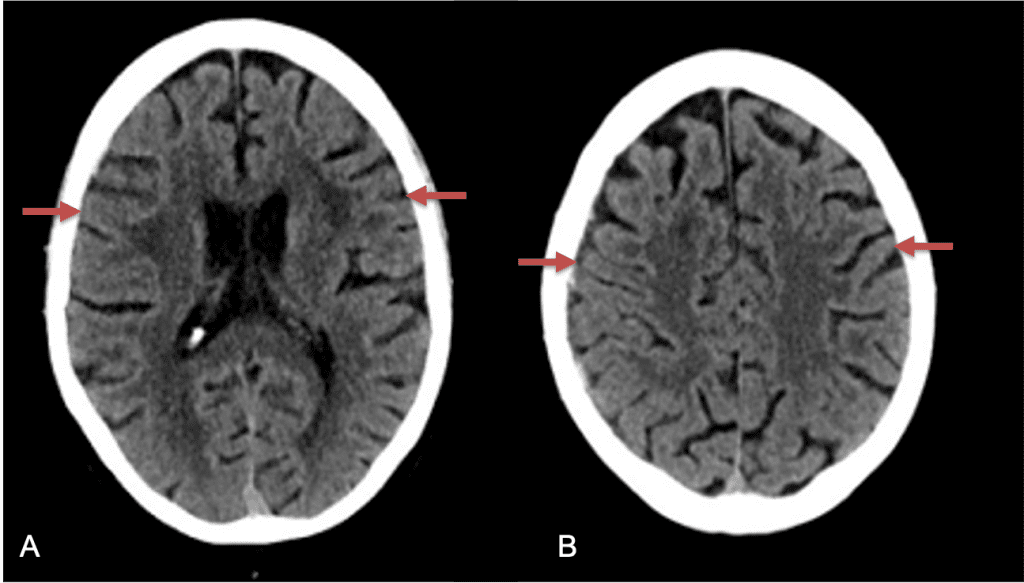

Clinically, the patient improved over the few weeks with the occasional transient twinge of a headache, but resolution of dizziness. Follow-up CT at 10 weeks demonstrated complete resolution of the bilateral subdural hematomas with our patient completely asymptomatic and back to all of her activities of daily living. Considering her history of thrombocytopenia and CLL, we will continue to monitor her into the future and are excited about her progress and recovery. (Figure 4. A and B)

Figure 4. A and B) – 10 weeks following embolization demonstrates complete resolution of bilateral collections both acute and chronic.